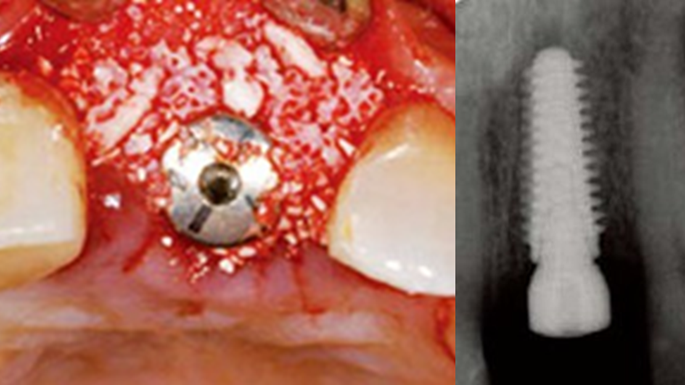

Clinical case: Bone filling into the bottom of deepest thread at 8.0mm AnyRidge fixture

- Courtesy of Dr. Kwang Bum Park -

AnyRidge, Knifethread ,extraction socket, ,initial stability ,Allograft, ,osseointegratio ,Dr. Kwang Bum Park, , Mandibular, Single replacement, AnyRidge, Mega-oss,

Implant system-AnyRidge, Regeneration-Mega-Oss

“AnyRidge implant enables fast and stable

osseointegration at this extreme case of bone defect. ”